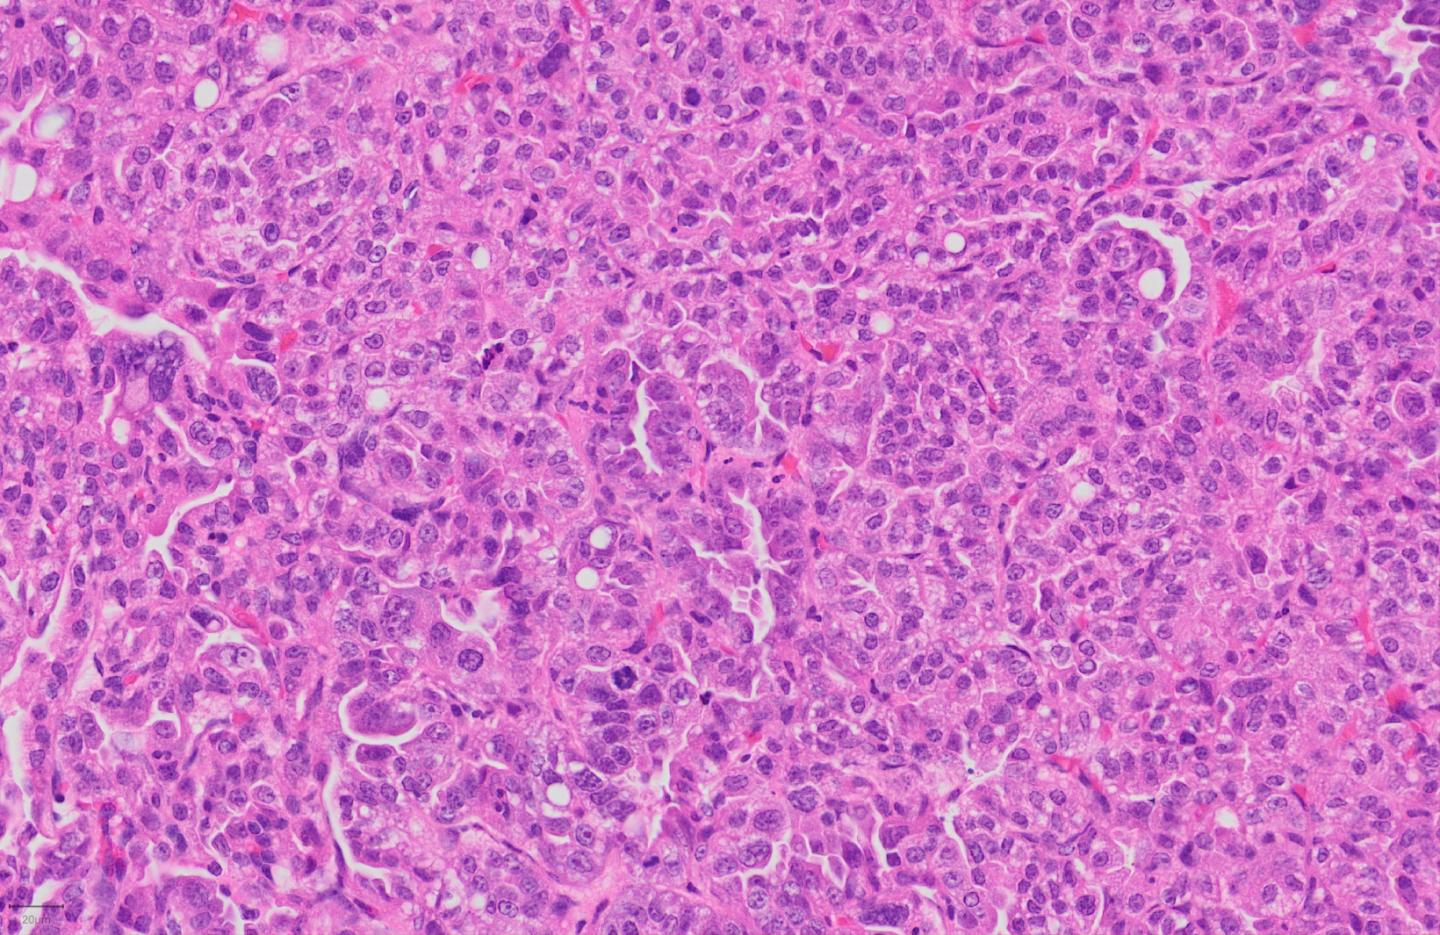

image: Histological staining of a lung adenocarcinoma, which is made of tumor cells as well as cells of the immune microenvironment including tumor-associated neutrophils.

Cancers are not only made of tumor cells. In fact, as they grow, they develop an entire cellular ecosystem within and around them. This "tumor microenvironment" is made up of multiple cell types, including cells of the immune system, like T lymphocytes and neutrophils.

But there is another type of immune cell in the tumor microenvironment whose importance in cancer development has been overlooked: neutrophils, which form part of the body's immediate or "innate" immune response to microbes. The question, currently debated among scientists, is whether neutrophils help or inhibit the tumor's growth.

Focusing on glucose metabolism in a genetically-engineered mouse model of lung adenocarcinoma, the scientists isolated tumor-associated neutrophils (TANs) and compared them to neutrophils from healthy lungs.